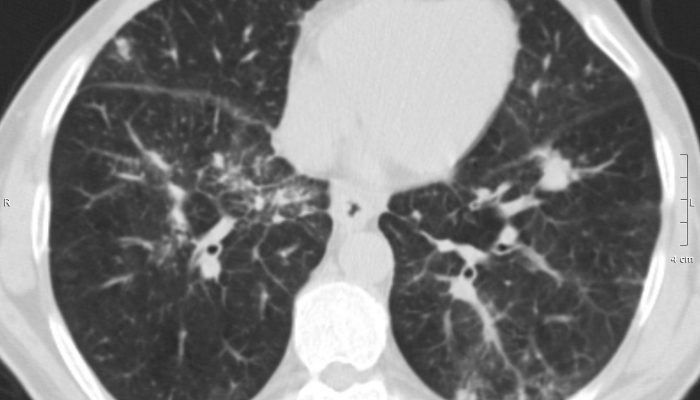

Быстро прогрессирующая интерстициальная пневмония представляет собой серьезное заболевание. Ее признаки включают высокую температуру, сухой и продолжительный кашель, а также затрудненное дыхание. Если своевременное лечение не будет проведено, то через несколько дней может возникнуть дыхательная недостаточность. Рентгенологическое обследование часто показывает наличие двустороннего распространенного затемнения легких, и основной метод диагностики заключается в изучении гистологического материала.

Используя рентгенографию, выявляются одинаковые изменения в легких на их краях («мутное стекло»).

Острая

Этот вид пневмонии начинается внезапно, симптомы напоминают грипп – повышается температура, появляются озноб и мышечные боли. Очень быстро развивается сильная одышка, которая может привести к нарушению дыхания и в тяжелых случаях потребовать использования искусственной вентиляции легких. Характер течения болезни схож с респираторным дистресс-синдромом у взрослых, на рентгенограмме наблюдается характерное для этого синдрома обширное затемнение обоих легких.

Отличительной особенностью является образование «матового стекла» на рентгеновском снимке. Прогноз благоприятный, и имеется возможность полного выздоровления.

Заболевание, которое начинается медленно и проявляется постепенным усилением симптомов. При прослушивании легких можно услышать двусторонние хрипы, а на рентгеновском снимке будет видна картина «матового стекла».

Один из очень полезных и информативных методов исследования — это рентгенография легких и компьютерная томография. Эти методы доступны для всех и не требуют больших затрат. Когда у человека возникают проблемы с легкими, рентген или томография могут выявить некоторые патологические изменения. Можно заметить усиленный рисунок легких, деформацию (тени мелких очагов), а также уменьшение прозрачности легких. При развитии воспаления легочной ткани на снимках врач обнаружит фиброз и разрушение легочной ткани.